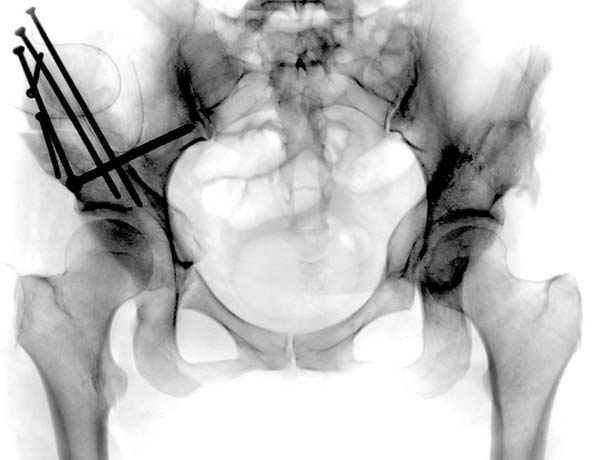

Рис.1 Трехмерная модель тазобедренного сустава с аналогом связки головки бедра. Заметно, что из торца головки выходит капроновый шнур, который с одной стороны прикрепляется к ножке бедренной части модели, а другой его конец, проходя через головку и прикрепляется к вертлужной части модели. Динамометр оказывается не нагруженным, так как аналог связки головки бедра замыкает подвижный узел модели во фронтальной плоскости.

Рис.2 Та же трехмерная модель тазобедренного сустава без аналога связки головки бедра. Пружина динамометра удерживает тазовую часть модели от опрокидывания, поддерживая стабильность так же, как отводящие мышцы обеспечивают ее в отсутствии связки головки бедра.